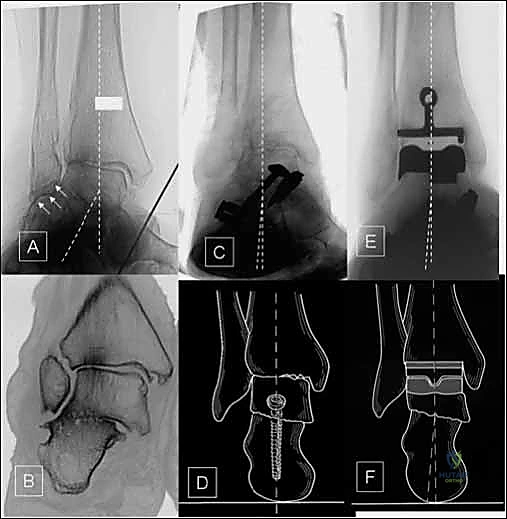

- الأشعة السينية (X-rays) بوضعية الوقوف: وهي الأداة الذهبية للتشخيص. صور الأشعة والوزن محمل على القدم (Weight-bearing X-rays) تظهر بدقة مدى تآكل الغضروف (ضيق المسافة المفصلية)، وجود نتوءات عظمية (Osteophytes)، وأي انحراف في المحور الميكانيكي للساق.

- الأشعة المقطعية (CT Scan): نلجأ إليها لفهم البنية العظمية ثلاثية الأبعاد بشكل أفضل، خاصة في حالات التشوهات المعقدة أو التخطيط الدقيق للقصات العظمية قبل الجراحة.

* التصميم الميكانيكي: يُعرف بأنه نظام ذو "مكون متحرك" (Mobile-bearing). يتكون من ثلاثة أجزاء رئيسية:

1. مكون معدني يثبت في أسفل عظمة الساق (Tibia).

2. مكون معدني يثبت في أعلى عظمة الكاحل (Talus).

3. قطعة بلاستيكية من البولي إيثيلين عالي الكثافة (Polyethylene insert): هذه القطعة ليست ثابتة، بل تنزلق بحرية بين المكونين المعدنيين.

* التثبيت: هو مفصل "غير إسمنتي". يتم تغطية الأسطح المعدنية الملامسة للعظم بطبقة مسامية من التيتانيوم وهيدروكسي أباتيت (Hydroxyapatite). هذه الطبقة تشجع العظم الطبيعي للمريض على النمو داخل مسام المفصل (Bone Ingrowth)، مما يوفر تثبيتاً بيولوجياً صلباً يدوم لسنوات طويلة.

* التصميم الميكانيكي: يشارك هذا النظام نفس الهندسة التشريحية الممتازة للمكونات المعدنية لنظام سالتو، ولكن مع اختلاف جوهري واحد: المكون البلاستيكي (البولي إيثيلين) هنا ثابت (Fixed-bearing) ويتم قفله بإحكام داخل المكون المعدني العلوي (الظنبوبي).